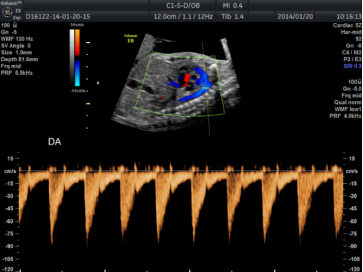

| 测量参数 | PW:静脉导管血流频谱(图3)。 |

图3 胎儿静脉导管血流频谱